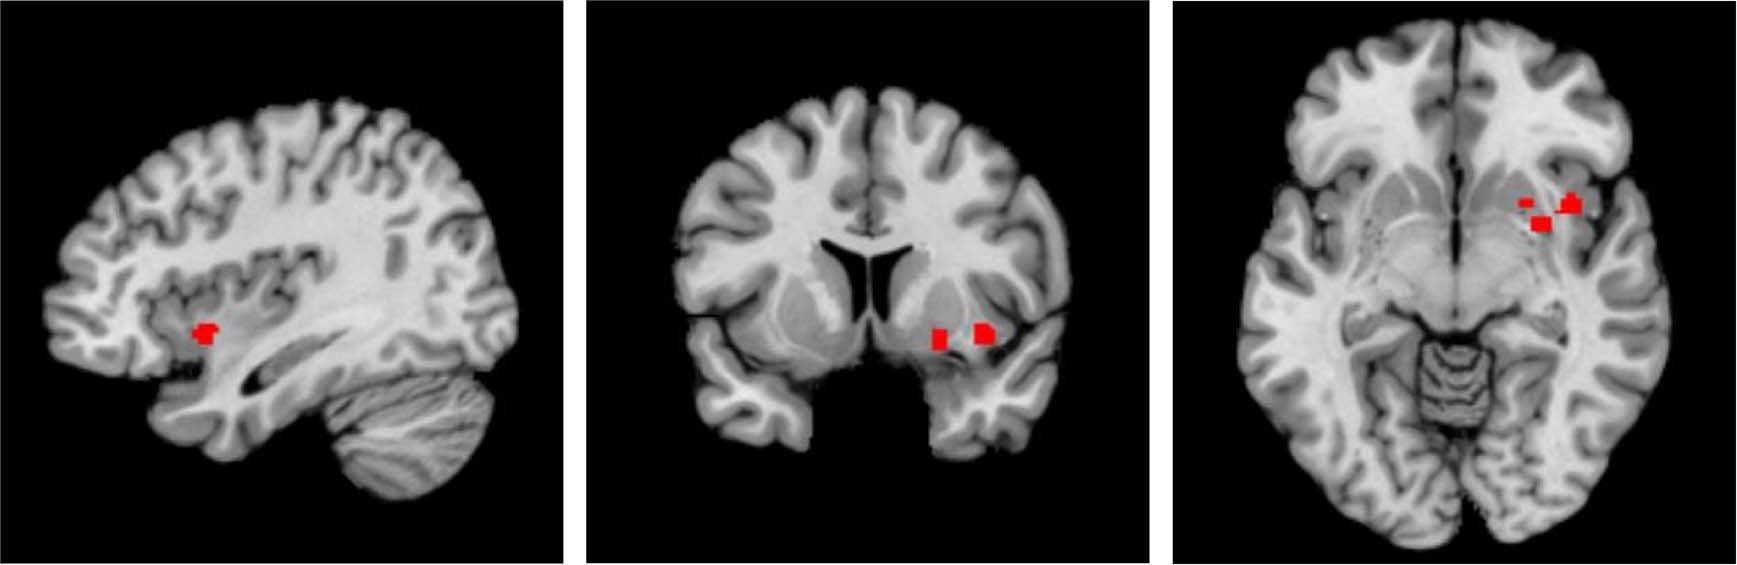

Fig. 3: The result of the sensitivity analysis of voxel-based morphometry studies showing the location of the cluster of significant grey matter volume reduction in the left hemisphere, centred in the claustrum and also including the putamen and insula, in hallucinators compared to non-hallucinators.

The location of the significant cluster, in sagittal (left), coronal (middle) and axial (right) planes, are highlighted in red.